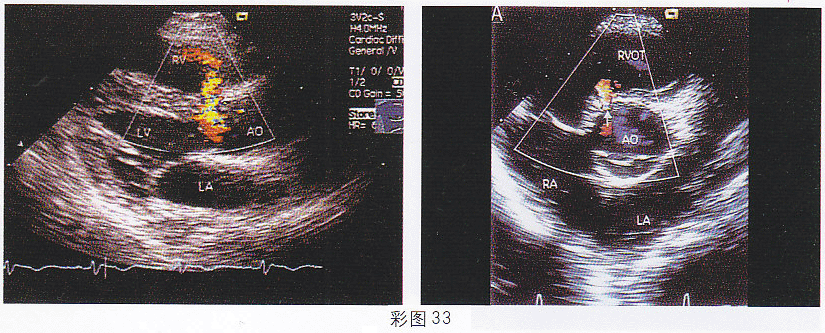

3.患兒,1歲,男,體檢發現胸骨左緣全收縮期雜音,超聲檢查如圖(彩圖33)所示。該圖所示的室間隔缺損屬于哪型

正確答案:A 解題思路:室間隔膜部缺口處探及過隔血流信號。

4.該病例最可能的診斷(彩圖4)

正確答案:D 解題思路:室間隔膜部呈瘤樣膨出并見缺損,缺口處探及高速過隔血流信號。